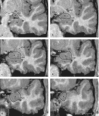

Figure 2.

Series of coronal images arranged from caudal (a) to rostral (f), indicating boundaries of the amygdala. A, Amygdala; AC, anterior commissure; H, hippocampus; EC, entorhinal cortex; EXC, external capsule; MS, medial surface of the brain; OT, optic tract; PU, putamen; SAS, semiannular sulcus; SI, substantia innominata; VC, ventral claustrum; WM, subamygdaloid white matter.